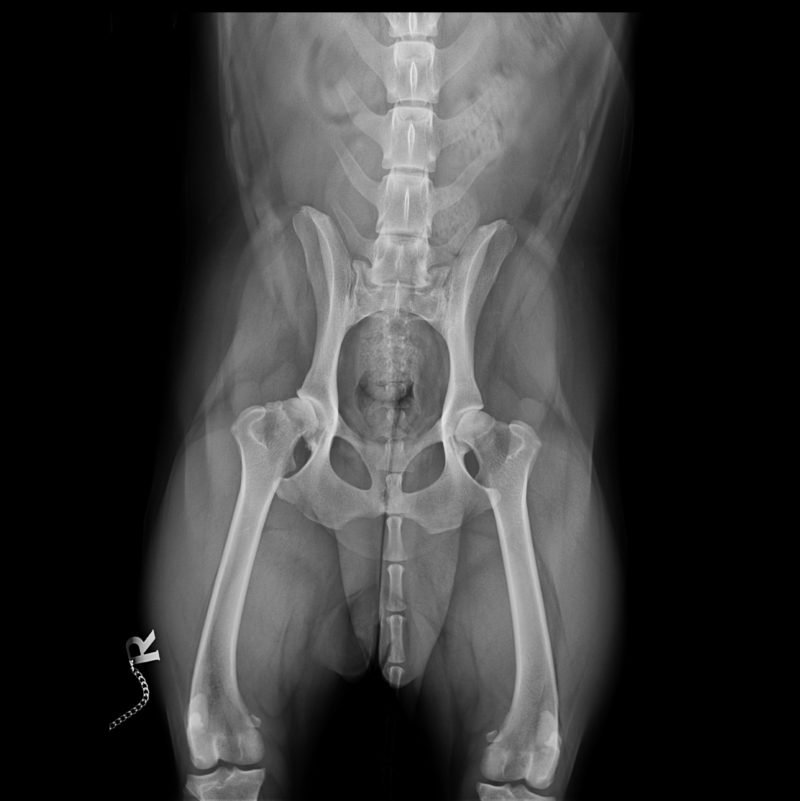

Bei genauerer Untersuchung des gesamten Bewegungsapparates im Gehen, Traben und auch durch Abtasten wurde allerdings schnell klar, dass der rechte Ellbogen nicht Bonnies einziges Problem war. Bonnie ging beim Vorlaufen (Gangbildanalyse) insgesamt recht steif, vorne übermäßig breit, hinten sehr eng und mit der Hinterhand nach rechts versetzt. Die Lahmheit zeigte sich im Trab deutlicher als im Schritt, beim Abtasten reagierte Bonnie druckschmerzhaft am rechten Ellbogen, an einzelnen Zehengelenken vorn beidseits, an den Schultergelenken, der gesamten Wirbelsäule, der rechten Hüfte und geringgradig an beiden Kniegelenken. Alle auffälligen Stellen wurden daraufhin geröntgt. Röntgenologisch fanden wir bei Bonnie, entsprechend der Schwere der Befunde absteigend geordnet:

- Hüftgelenksdysplasie und -arthrosen beidseits